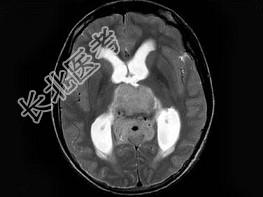

- 单项选择题男,16岁, 头痛数月,MRI平扫及增强扫描如图, 最可能的诊断是 ( )

A、生殖细胞瘤

B、松果体细胞瘤

C、星形细胞瘤

D、室管膜瘤

E、未见异常